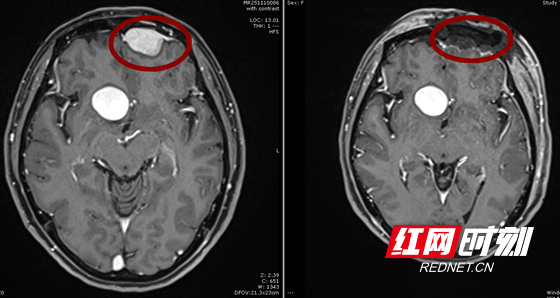

脑膜瘤手术前后对比图。

2025年10月,她再次找到湘雅常德医院神经外科刘景平教授复查。通过相关影像学检查结果显示:患者颅内不仅有一个2.6cm的脑膜瘤,还有1枚直径近3CM的巨大动脉瘤及6个多发小动脉瘤分布在颅内两侧血管。